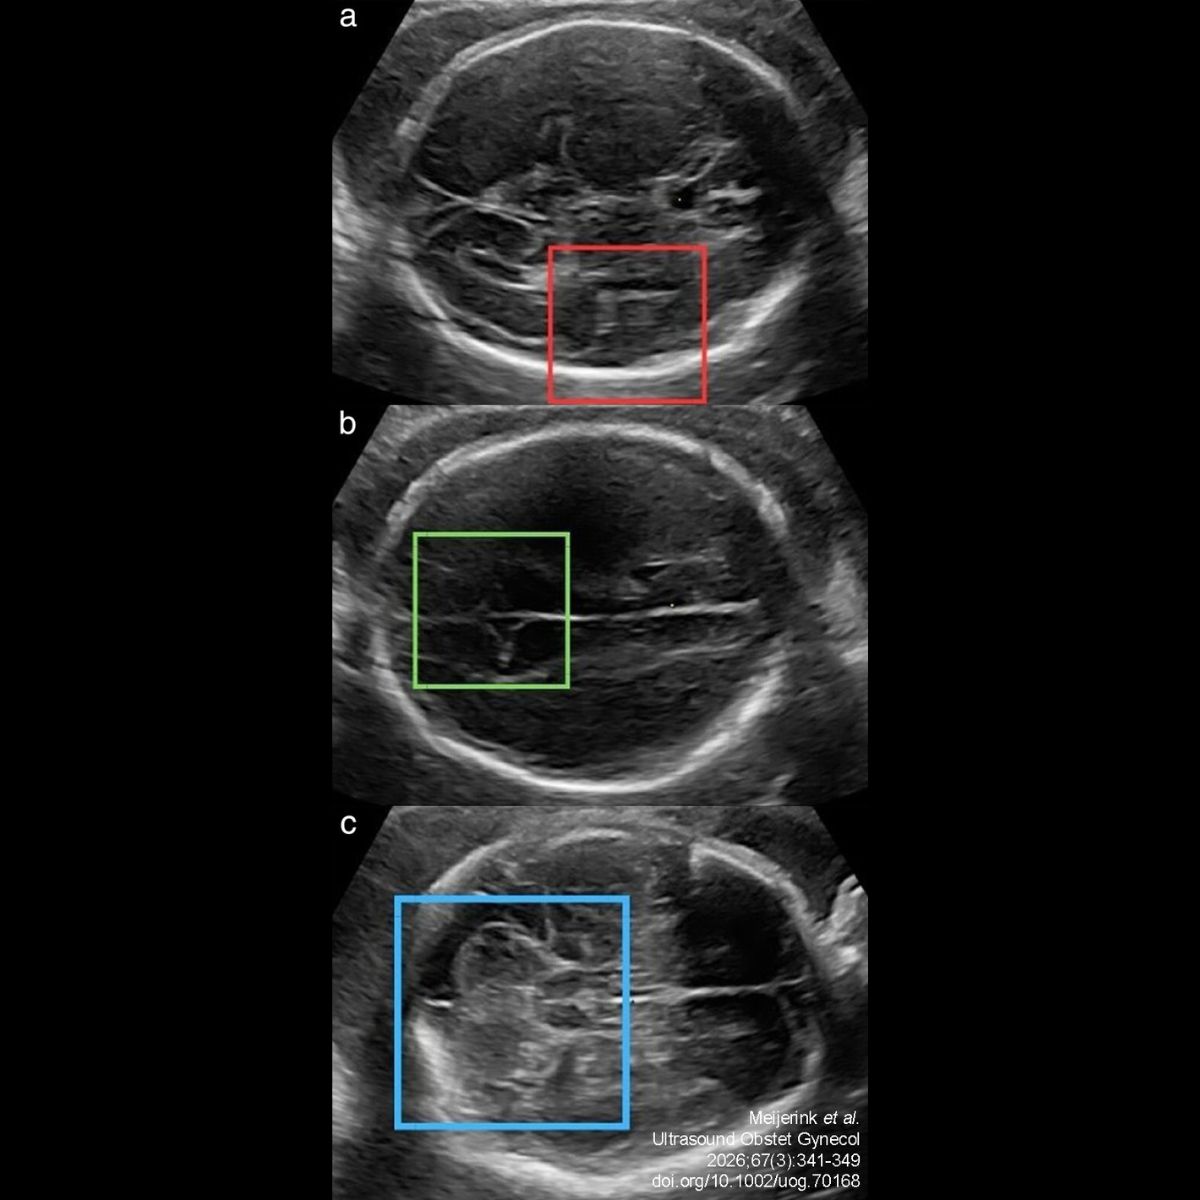

“In a new openaccess study, Meijerink et al. demonstrate delayed fetal brain maturation in early-onset fetal growth restriction using a 3D ultrasound deep-learning model, demonstrating the potential role of these models in future neurodevelopmental assessment.

Title:Deep learning assessment of fetal brain maturation on 3D ultrasound volumes in early-onset fetal growth restriction

Authors:L. Meijerink, M. Wyburd, A. I. L. Namburete, T. Alderliesten, F. Groenendaal, M. Benders, F. Terstappen, M. N. Bekker